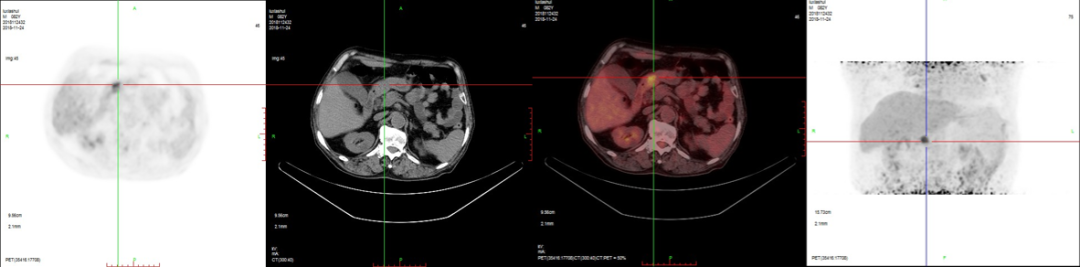

病例3:男性,72歲。結(jié)腸腺癌術(shù)后3年,右肺鱗癌術(shù)后1年隨訪。

PET/CT檢查:

1、全身多發(fā)骨轉(zhuǎn)移;

2、右側(cè)鎖骨區(qū)、縱膈及左側(cè)肺門多發(fā)淋巴結(jié)轉(zhuǎn)移;

3、腹膜后淋巴結(jié)轉(zhuǎn)移待排;

4、肝脾多發(fā)轉(zhuǎn)移灶可能。